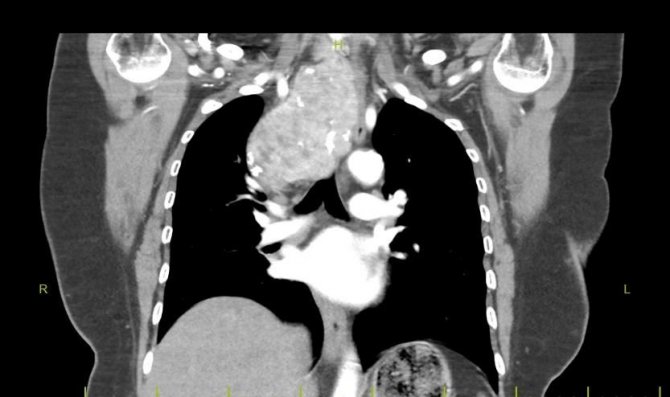

Boyunda kitlesi nedeniyle nefes darlığı ve yutma güçlüğü şikayetleriyle hastanelere başvuran hasta, riskli ameliyat nedeni ile Fethi Sekin Şehir Hastanesi Genel Cerrahi Polikliniği'ne yönlendirildi. Yıllar önce guatr hastalığına bağlı tiroid ameliyatı geçirdiği öğrenilen hastanın yapılan tetkiklerinde, guatr hastalığının nüks ettiği ve 8 x 12 santimetrelik nüks guatr kitlesinin boyundan göğüs kafesine doğru uzandığı görüldü. Nüks guatr kitlesinin solunum yollarına, ana damarlarına ve yemek borusuna baskı yaptığı saptandı.